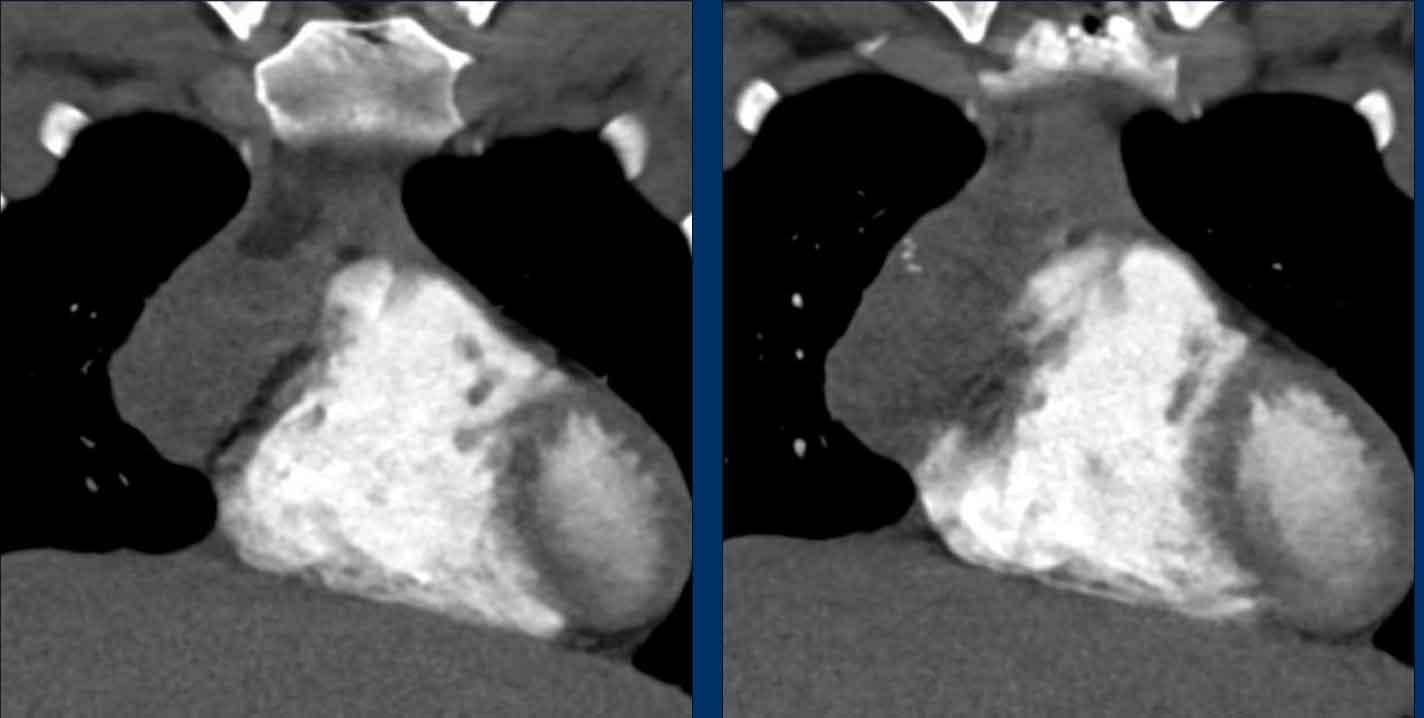

Mặc dù không thực sự cần thiết, MRI vẫn được thực hiện.

Hình ảnh

Hình ảnh chuỗi xung gradient-echo nhanh pha đối (out-of-phase) cho thấy sự mất tín hiệu như dự kiến.

CT cho thấy tuyến ức trở về bình thường sau khi điều trị bệnh Graves.

Khi đo cường độ tín hiệu, bạn sẽ nhận thấy sự sụt giảm cường độ tín hiệu.

Tỷ lệ phần trăm sụt giảm tín hiệu này được gọi là chỉ số cường độ tín hiệu (SII).

Chỉ số cường độ tín hiệu

Chỉ số cường độ tín hiệu (SII) là lượng tín hiệu bị mất đi chia cho lượng tín hiệu ban đầu.

SII lớn hơn 9% có độ nhạy và độ đặc hiệu 100% trong chẩn đoán tăng sản tuyến ức.

SII đáng tin cậy hơn so với tỷ số dịch chuyển hóa học.

Trong trường hợp này, SII là 77%.